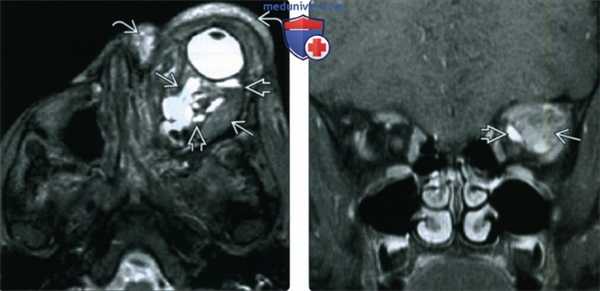

(Слева) При КТ с КУ в аксиальной проекции определяется дольчатое ретробульбарное объемное образование, повторяющее контуры (по типу «отливки») задней части правого глазного яблока лишь минимально уплощающее контур склеры. Эта MALT-лимфома характеризуется гомогенными плотностью и контрастированием.

(Справа) При Т1 МРТ с КУ в корональной проекции вне мышечного конуса визуализируется гомогенно контрастируемая MALT-лимфома, поражающая слезную железу и простирающаяся кзади вдоль наружной прямой мышцы. Обратите внимание на наличие внутричерепной супраселлярной опухоли. (Слева) При МРТ в режиме STIR в корональной проекции у женщины 50 лет в правой слезной железе определяется слегка гиперинтенсивное овоидное объемное образование с четкими контурами. Обратите внимание на прилегающий небольшой участок потери сигнала.

(Справа) При аксиальной МРТ Т1 FS с КУ у этой же пациентки определяется гомогенное контрастирование объемного образования левой слезной железы. При патологоанатомическом исследовании диагностирована лимфоидная гиперплазия. Проведено успешное лечение - выполнялись местные инъекции стероидов.

(Слева) При МРТ Т1 в аксиальной проекции глазниц определяются обширные двусторонние дольчатые инфильтративные мягкотканные объемные образования, прорастающие во внутриконусное и экстракональное пространства.

(Справа) При МРТ Т1 FS с КУ в корональной проекции у этого же пациента отмечается диффузное контрастирование инфильтративной ткани. Визуализируются двусторонние новообразования слезных желез Ев, а также поражение мышечного конуса, структур внутри и вне его.

(Слева) При MPT Т1 FS с КУ в корональной проекции определяется типичная картина MALT-лимфомы: гомогенное контрастируемое объемное образование внутри мышечного конуса. Опухоль окружает зрительные нерв и потенциально может симулировать менингиому.

(Справа) При КТ с КУ в аксиальной проекции в медиальной области глазницы определяется гомогенно контрастируемое объемное образование, вызывающее тяжелый экзофтальм и конусообразную деформацию левого глазного яблока. Эта мантийноклеточная лимфома более агрессивна по сравнению с типичной MALT-лимфомой глазницы и вызвала деструкцию большей части левого решетчатого лабиринта.